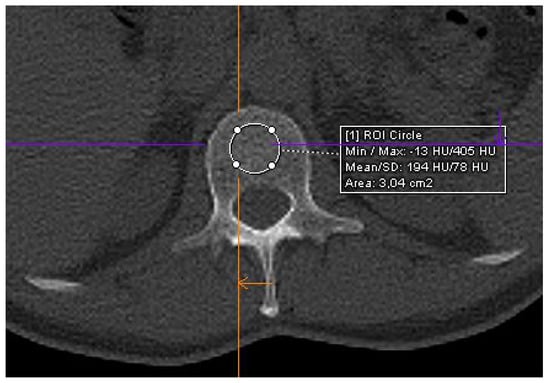

2.4. CT Imaging